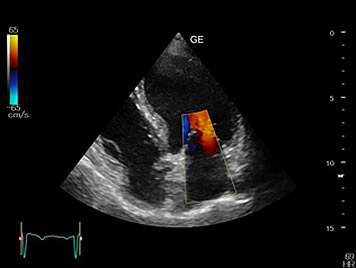

EWH provides full ultrasound services and we look forward to creating a welcoming and comfortable environment for you.

Our professionals at EWH are trained to use state of the art ultrasound technology to provide ultrasound diagnoses